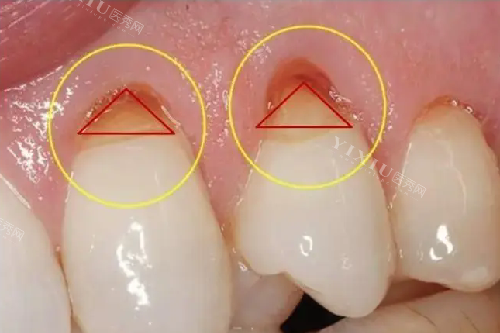

特色项目首推“儿牙早期干预矫正”,杨正辉医生团队采用MRC肌功能矫治器等工具,针对3-12岁孩子的地包天、龅牙等问题早期干预,通过调整口腔肌肉功能引导牙齿正常生长,相比成年后矫正,疗程更短、创伤更小,适合家长早发现早干预。